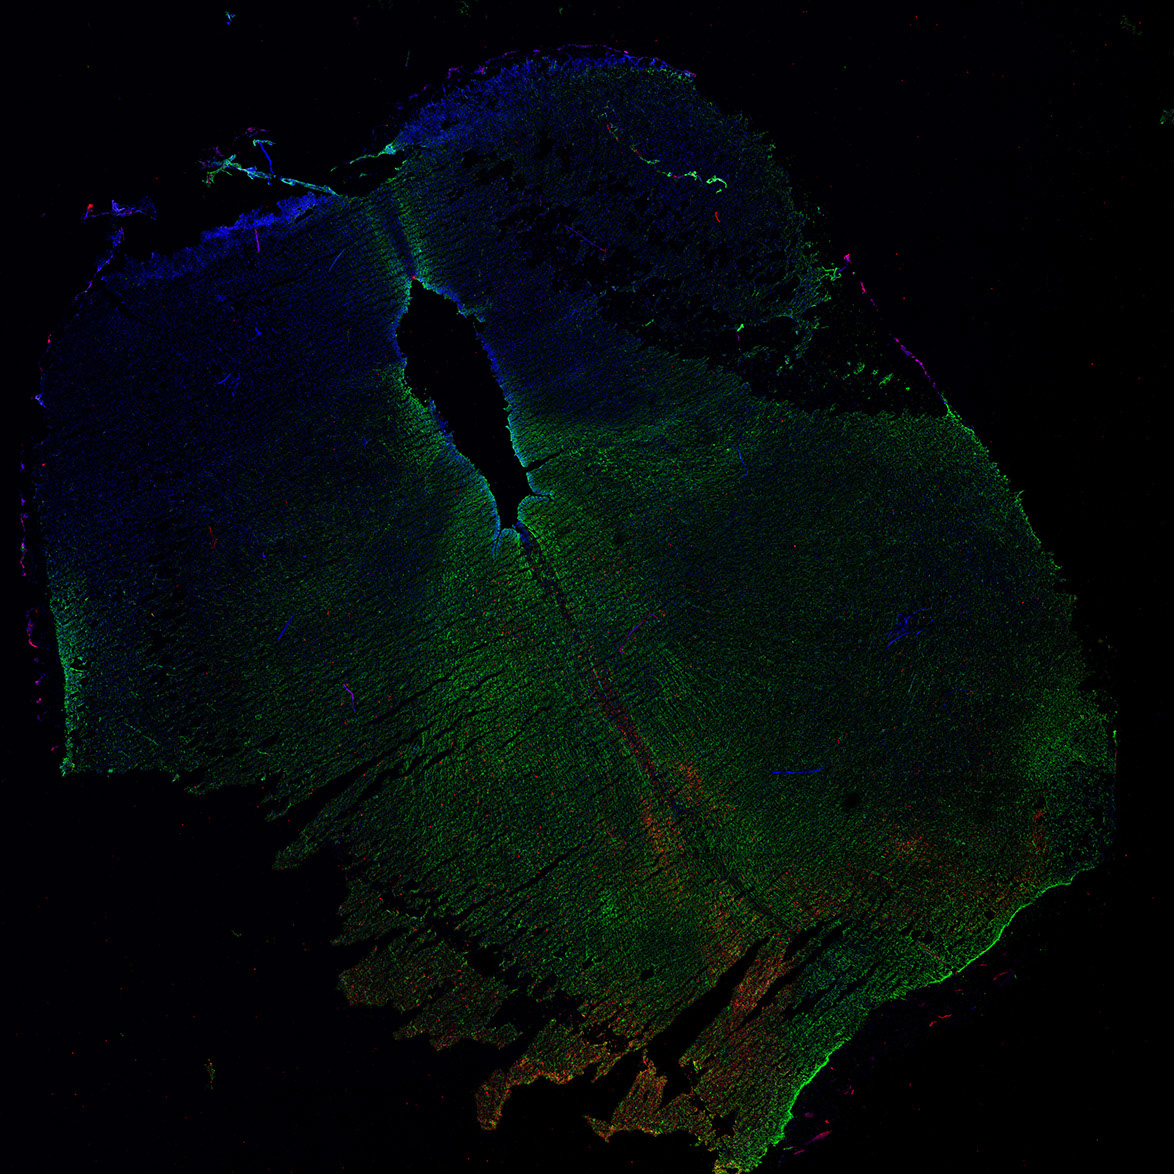

17PCW

DAPI

17PCW human midbrain

MAP2

TH

Merged